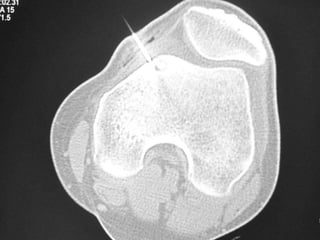

Post op – after drilling

CT – Guided Drilling

•

OPD procedure,

Localization of the nidus in CT Scan,

Local anesthesia,

K-wire passed into nidus,

Transferred to OT,

Short GA,

Drilling of the nidus by a cannulated drill,

Complete relief of pain.

Post op –after drilling

CT – GuidedDrilling • • • • • • • • OPD procedure, Localization of the nidus in CT Scan, Local anesthesia, K-wire passed into nidus, Transferred to OT, Short GA, Drilling of the nidus by a cannulated drill, Complete relief of pain.